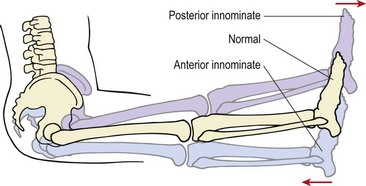

Positional faults of the innominates 276

image

Figure 13.26 Leg length assessment of sacroiliac joint.

From Magee (2002) with permission.

Treatment is aimed at the more painful side. Where anterior rotation occurs (leg shorter) the treatment is to posteriorly rotate the innominate (see below). Where anterior rotation has occurred (leg longer) it is thought that an upslip has occurred and this should be treated using leg traction (Turner, 2002).

Keypoint

During a sit-up test, if the leg gets shorter the treatment is to posteriorly rotate the innominate (pelvic bone). If the leg gets longer, leg traction should be used.

Page 276

Positional faults of the innominates

Three main positional faults occur in the SIJ, anterior innominate (common), upslip (common) and posterior innominate (less common) (Fig. 13.27). A variety of other appearances occur but they are not as frequently seen in day-to-day clinical practice. The reader is referred to Lee (1994) for further information.